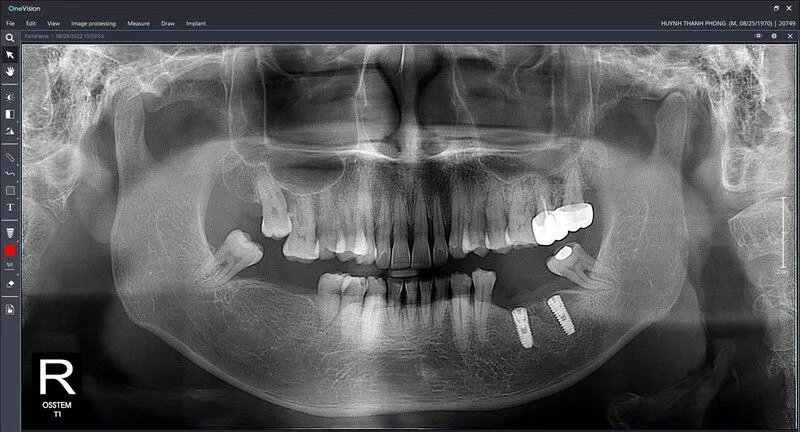

Trước khi trả lời câu hỏi chụp CT Conebeam ở đâu Hải Phòng, hãy cùng tìm hiểu tổng quan về phương pháp nha khoa này. Chụp CT Conebeam (Cone Beam Computed Tomography – CBCT) là một công nghệ hình ảnh tiên tiến sử dụng tia X để tạo ra hình ảnh 3D cực kỳ chi tiết của các cấu trúc trong vùng hàm mặt. Trong đó bao gồm răng, xương hàm, mô mềm và ống thần kinh. Khác với các phương pháp chụp X-quang truyền thống chỉ cho phép quan sát hình ảnh 2D phẳng, CT Conebeam cung cấp một “bản đồ” 3D toàn diện, cho phép nha sĩ nhìn thấy các mô và cấu trúc xung quanh từ nhiều góc độ khác nhau. Điều này giúp cải thiện độ chính xác trong việc chẩn đoán và lập kế hoạch điều trị.

Hệ thống Conebeam kết nối máy tính và phần mềm chuyên dụng để xử lý dữ liệu, tạo ra các hình ảnh sắc nét và dễ dàng phân tích. Với khả năng cung cấp thông tin chi tiết về xương hàm và mô mềm, phương pháp này là công cụ hỗ trợ đắc lực trong nhiều lĩnh vực nha khoa, từ cấy ghép implant, chỉnh nha, cho đến phẫu thuật hàm mặt. Bằng cách này, các bác sĩ có thể đưa ra những quyết định điều trị chính xác và an toàn hơn, giảm thiểu rủi ro và nâng cao hiệu quả điều trị.

- Cấy ghép Implant: Một trong những ưu điểm lớn của CT Conebeam là khả năng đánh giá mật độ xương tại khu vực cấy ghép. Bằng cách sử dụng hình ảnh 3D, bác sĩ có thể quyết định liệu có cần ghép xương hay không và chọn đường kính implant phù hợp nhất với ổ xương. Nếu không sử dụng CT Conebeam, bác sĩ có thể chỉ chọn implant có đường kính nhỏ nhất để đảm bảo an toàn. Tuy nhiên, điều này có thể không tối ưu cho tuổi thọ lâu dài của implant.